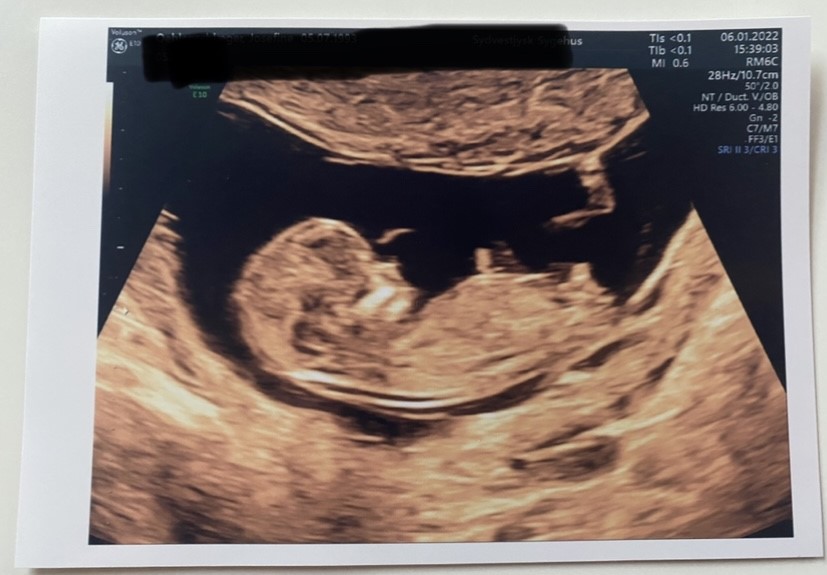

Vi ville IKKE vide kønnet, men jeg er ret kendt med Nub terorien, og vi fik dette billede med hjem.

Jeg synes jo, at det er SÅ tydeligt, at det er en lille dreng.

Men hvad siger panelet?

Det jeg tror at du ser som en meget tydelig tap, tænker jeg er lårbenet? Jeg tænker ikke at det er udelukket at det er en pige

Jeg tror også det er lårbenet du tænker er nubben. synes faktisk nærmere det ligner en pige nub under.. Så jeg vil gætte pige

Okay vildt nok. Jeg ser slet ikke at det kan være en pige  man kan se lårbenet i baggrunden og viljen er for skæv til at nubben ville kunne være låret.

Det er ikke fordi jeg tror det er en tap som en tissemænd? Det er fordi den stritter opad og ikke går henad som på piger. Altså ifølge nub teorien.